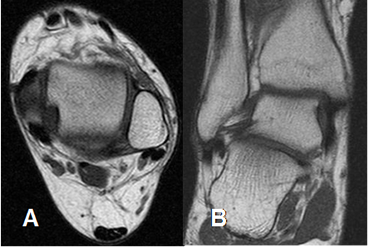

La Resonancia Magnética (RM) es el estudio de elección, para la valoración del tobillo y el pie. Permite estudiar las estructuras óseas y los tejidos blandos, que incluyen músculos y tendones, ligamentos, nervios, espacio articular, etc.

Las secuencias deben incluir cortes axiales, sagitales y coronales. En el tobillo los cortes se orientan en relación con la mesa de examen y en el pie, en relación con el eje longitudinal de los metatarsianos. (1). (Fig 6 y 7).

Fig 6. Orientación de los cortes en el tobillo.

A: RM axial y B: RM coronal.